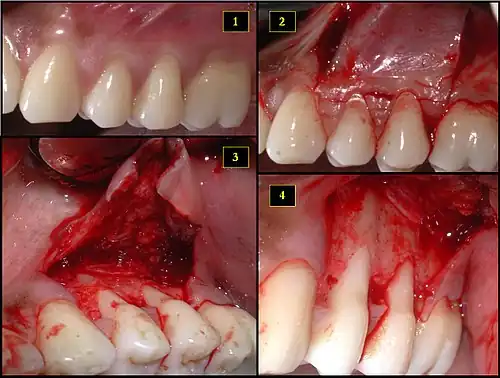

1. Ipsilateral palatal mucosa serving as the donor site

2. The retrieved connective tissue, approximately 25 × 6 mm in dimension

3. Connective tissue placed at recipient site

4. Recipient site flap coronally advanced and sutured to entirely cover the graft